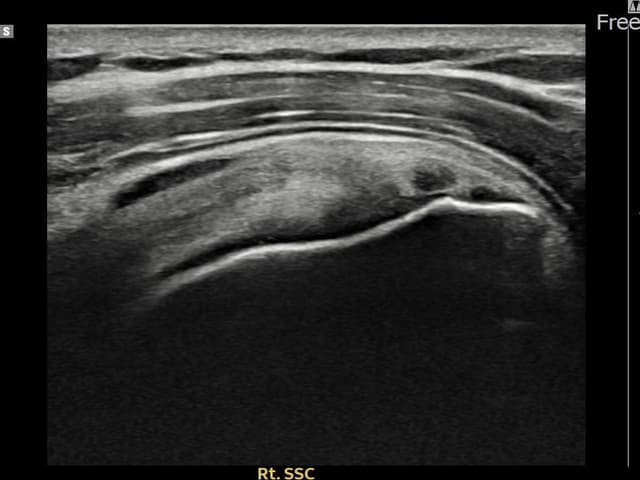

[経過期間: 24.03.04~24.05.10]

[縫縮術] 超音波検査にて右 견갑하근건 関節面側部分断裂(7mm × 3mm (腱厚の約28%欠損))を確認。縫縮術施行後、腱の連続性が回復し、日常生活に復帰されました。

[経過期間: 24.03.21~24.05.29]

[縫縮術] 超音波検査にて右 견갑하근건 部分断裂(8mm × 3mm (腱厚の約32%欠損))を確認。縫縮術施行後、腱の連続性が回復し、日常生活に復帰されました。